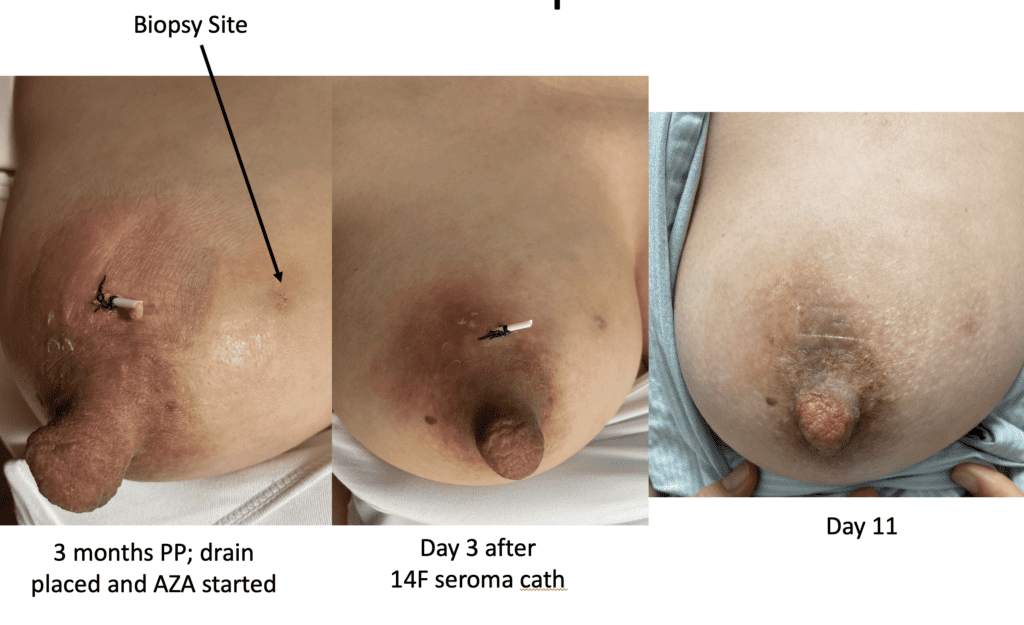

Idiopathic Granulomatous Mastitis (IGM or GM)

Idiopathic granulomatous mastitis (IGM) is an inflammatory disorder affecting the breast of young women in their childbearing years, and can overlap with lactation and pregnancy. It can result in development of painful inflammatory masses, fluid collections, and fistula formation. While breastfeeding from the affected breast in the setting of IGM is safe, many mothers report significant pain and difficulty with latch or milk production.

The definitive treatment for IGM is immunosuppression with the oral medications methotrexate (not safe with lactation or pregnancy) or azathioprine (safe with pregnancy and lactation). This case report describes continued breastfeeding and resolution of IGM with azathioprine therapy.

Mothers also may elect no treatment during lactation; fluid collections, fistula formation, and other symptomatology can be managed on an as-needed basis.

Drainage of recurrent fluid collection and injection of steroid:

While some cases of IGM may resolve from a simple mass, many go on to form fluid collections (above and below) that may drain on their own. These are mistakingly called “abscesses.” They are in fact just fluid collections of dead inflammatory cells. Patients need either local treatment with needle drainage of the fluid (NOT large incisions with packing tape, which make inflammation worse) and steroid injection, or oral steroids/anti-inflammatories/immune suppressants.